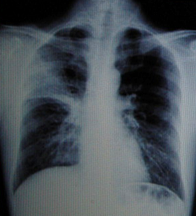

男性,40岁。发热4天,伴黄痰。

A.右上肺不张

B.右上肺炎

C.右上肺癌

D.右上胸膜肥厚

『正确答案』B